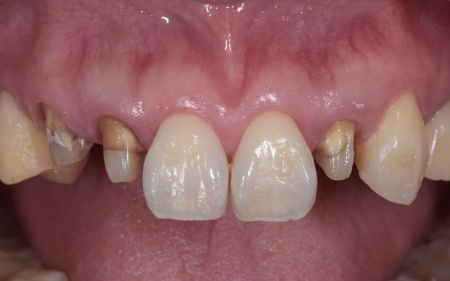

| カウンセリング | 拝見したところ、左下と右上の歯はともに大きな虫歯があり、歯だけでなく被せ物を支える土台の部分にも影響が及んでいました。

さらに、ほかの歯に入っている詰め物や被せ物の周囲にも、過去に治療した部分に再び虫歯ができる二次カリエスが複数見つかりました。 また、噛み合わせを確認したところ、奥歯で噛み合わせた際に上下の前歯が当たらず隙間ができる開咬(かいこう)が認められました。 実際に患者様の場合も、特定の歯に長期間強い力がかかり続けたことで歯や修復物の破損、さらには口腔内全体のトラブルにつながった可能性が高いと考えられました。 修復治療が必要でしたがこの噛み合わせの問題を改善しないまま行うと、治療した歯に再び過度な力が加わって被せ物の破損・脱離や虫歯の再発を招くリスクが高まります。 |